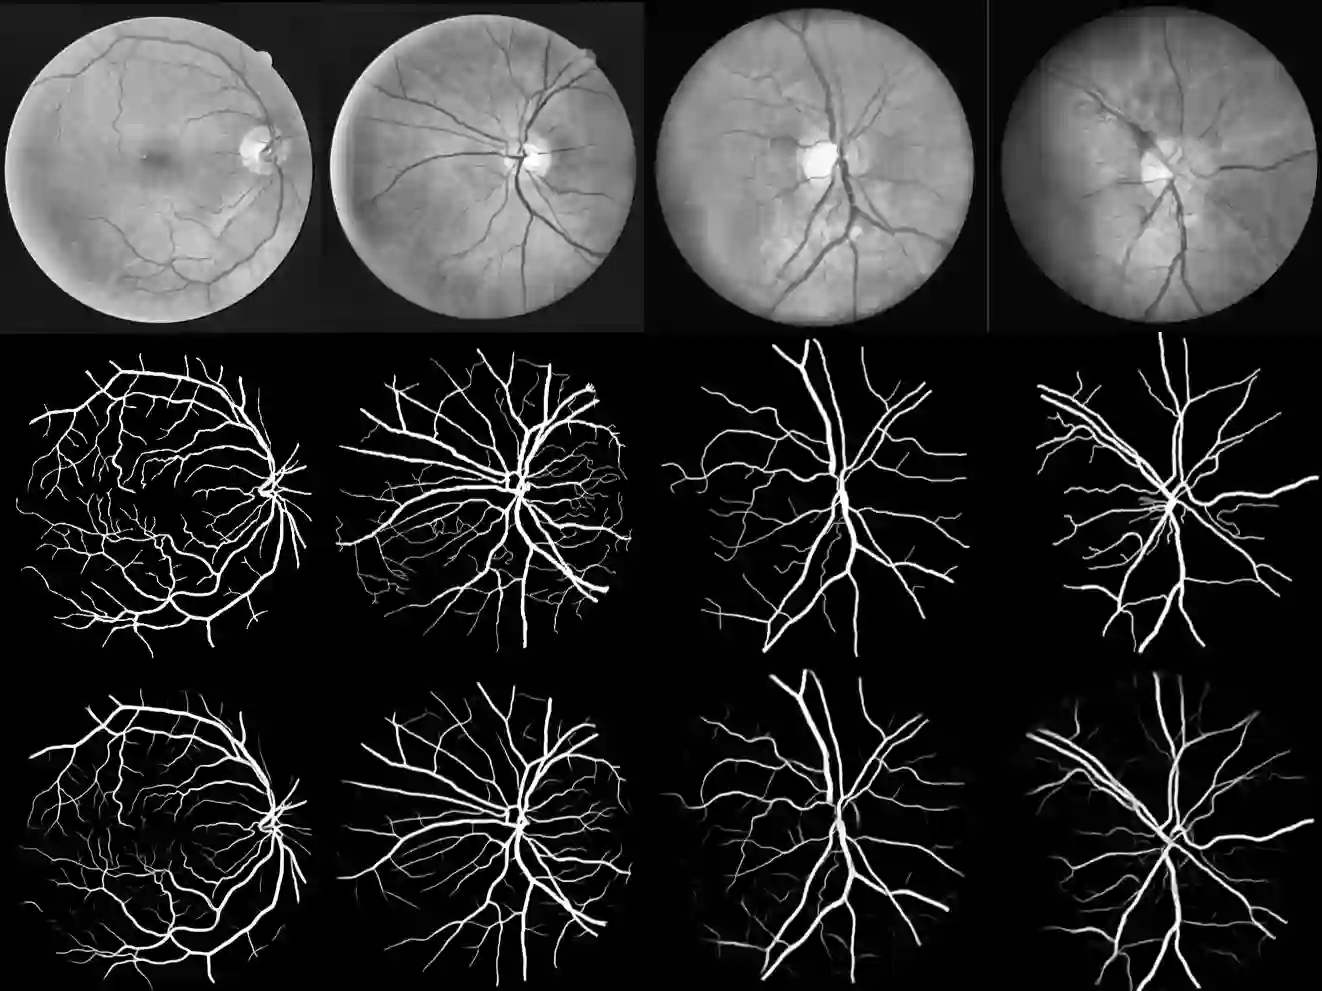

Segmentation of macro and microvascular structures in fundoscopic retinal images plays a crucial role in the detection of multiple retinal and systemic diseases, yet it is a difficult problem to solve. Most neural network approaches face several issues such as lack of enough parameters, overfitting and/or incompatibility between internal feature-spaces. We propose Attention W-Net, a new U-Net based architecture for retinal vessel segmentation to address these problems. In this architecture, we have two main contributions: Attention Block and regularisation measures. Our Attention Block uses attention between encoder and decoder features, resulting in higher compatibility upon addition. Our regularisation measures include augmentation and modifications to the ResNet Block used, which greatly prevent overfitting. We observe an F1 and AUC of 0.8407 and 0.9833 on the DRIVE and 0.8174 and 0.9865 respectively on the CHASE-DB1 datasets - a sizeable improvement over its backbone as well as competitive performance among contemporary state-of-the-art methods.